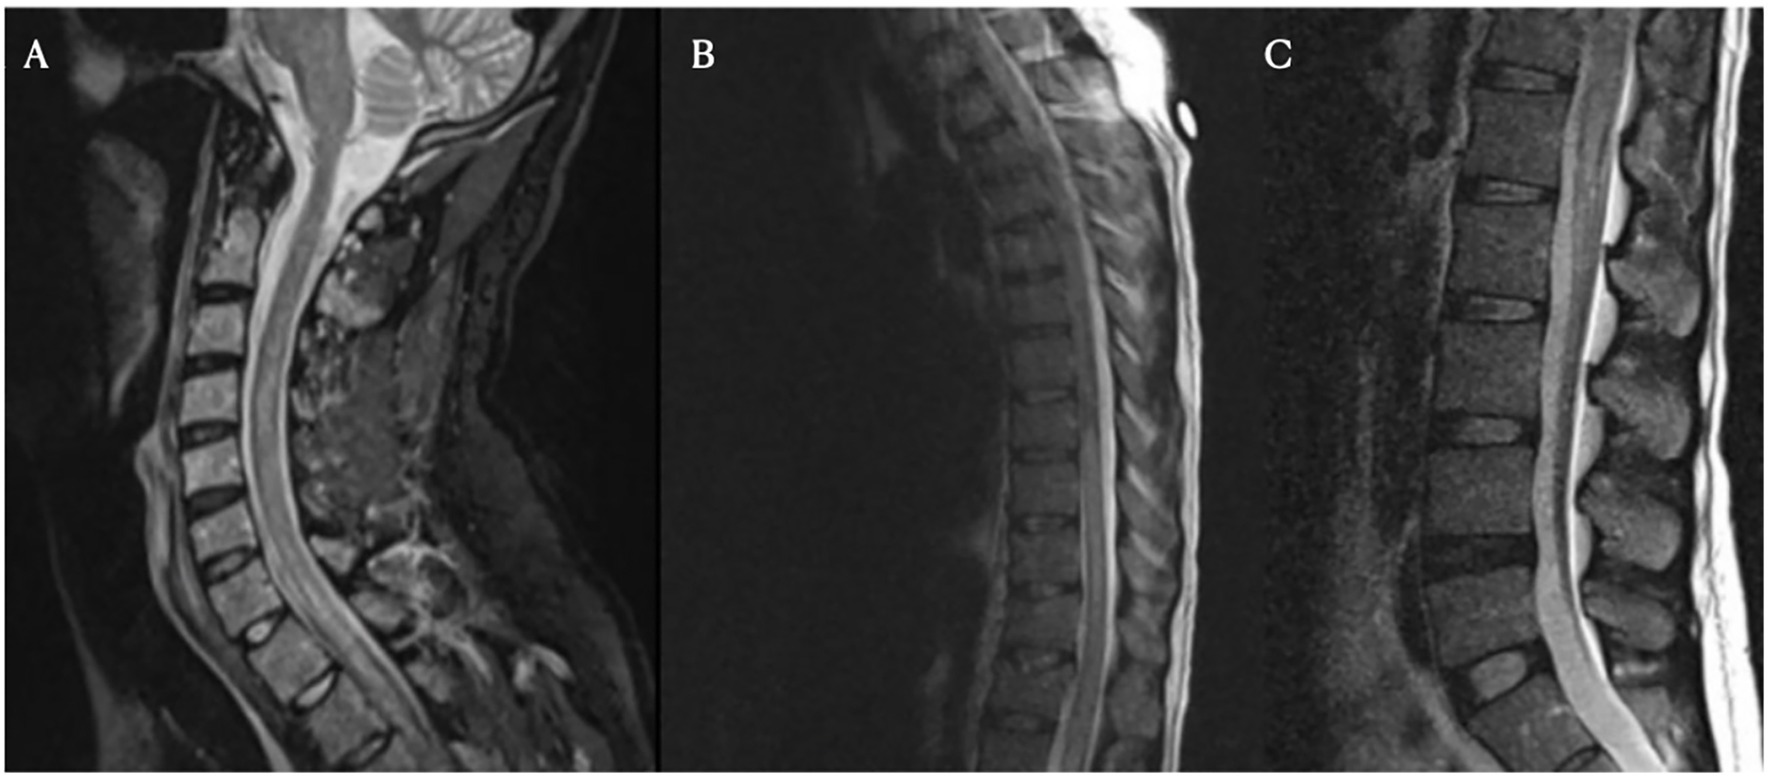

On day nine following Yescarta infusion, the patient was extubated and noted to have new-onset bilateral lower extremity paresis, areflexia, and sensory loss up to the level of the umbilicus. MRI revealed diffuse T2 hyperintensity throughout the cervical cord, thoracic cord, and conus medullaris (Figure 5). He was empirically initiated on intravenous immunoglobulin (IVIG, 0.4 g/kg for 5 days) while continuing dexamethasone and anakinra therapy. Although neuroimaging showed improvement with this regimen, the patient’s lower extremity weakness persisted without clinical recovery. By day 21, repeat MRI demonstrated complete resolution of the initial brain and spine abnormalities; however, new findings emerged in the conus medullaris, including clumping of the ventral nerve roots (Figure 6). Cerebrospinal fluid (CSF) analysis revealed elevated protein (101 mg/dL), leukocytosis (23 cells/μL), normal glucose (61 mg/dL), and no evidence of malignancy. Infectious cultures, ganglioside antibodies, aquaporin-4, paraneoplastic antibodies, and oligoclonal bands were all negative in the CSF.

Figure 5

Three spinal MRI images labeled A, B, and C. Image A shows the cervical spine with visible vertebrae and spinal cord. Image B focuses on the thoracic region, highlighting the spinal alignment. Image C displays the lumbar spine, illustrating vertebrae and intervertebral discs.

Figure 5. Spinal magnetic resonance imaging on day 10 post-treatment. Cervical (Panel A), thoracic (Panel B), and lumbar (Panel C) spine MRI images obtained on day 10. These images show longitudinally extensive T2 hyperintensity within the spinal cord, most prominent from C7 to T4 and from T8 to the conus medullaris. No significant spinal canal or neural foraminal stenosis is noted at any level.